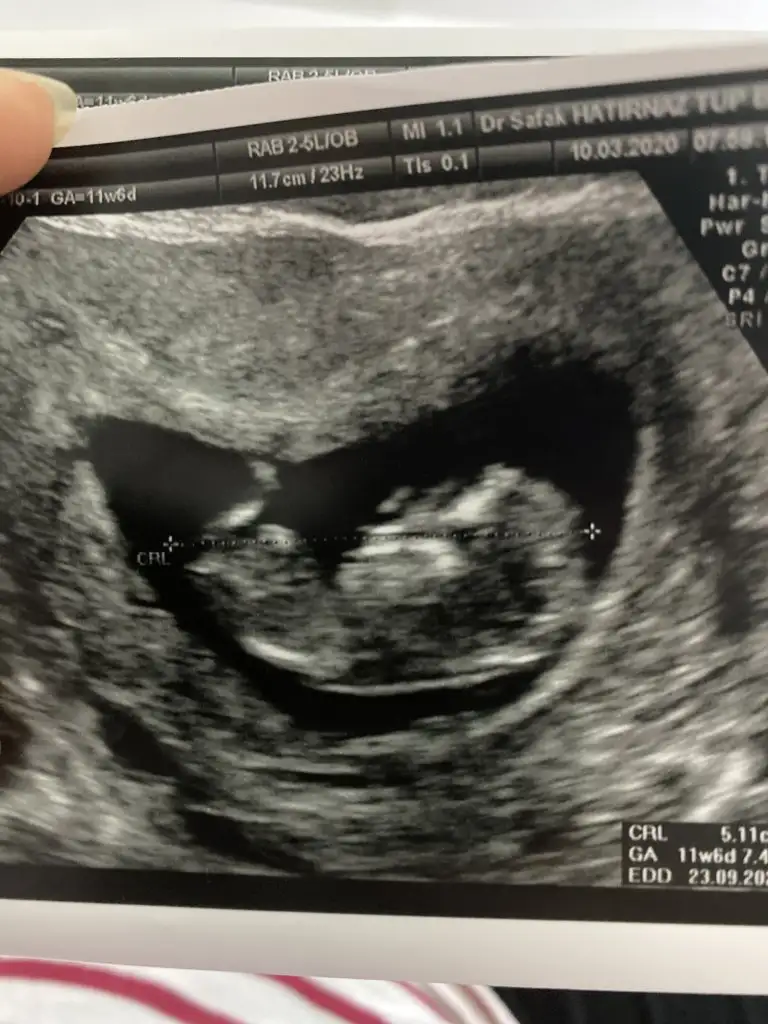

Sevgili @ıkrameyra cinsiyet tahmini alabilir miyim 🌹💕

BDA5C7BD-3496-4BB1-A970-938708FDFC4E.jpeg

Eklentiler

• 61A9F4EF-9683-43B4-B5BD-00CCB355CF56.webp

61A9F4EF-9683-43B4-B5BD-00CCB355CF56.webp

28,5 KB · Görüntüleme: 40

• C8D7EF01-26BB-4FC3-99CF-7FA7C7BDCC8C.webp

C8D7EF01-26BB-4FC3-99CF-7FA7C7BDCC8C.webp

37,8 KB · Görüntüleme: 49